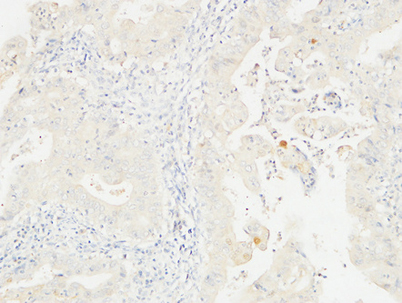

Dilutions: IHC-p: 100-300.Western Blot: 1/500 - 1/2000. ELISA: 1/20000. Not yet tested in other applications.